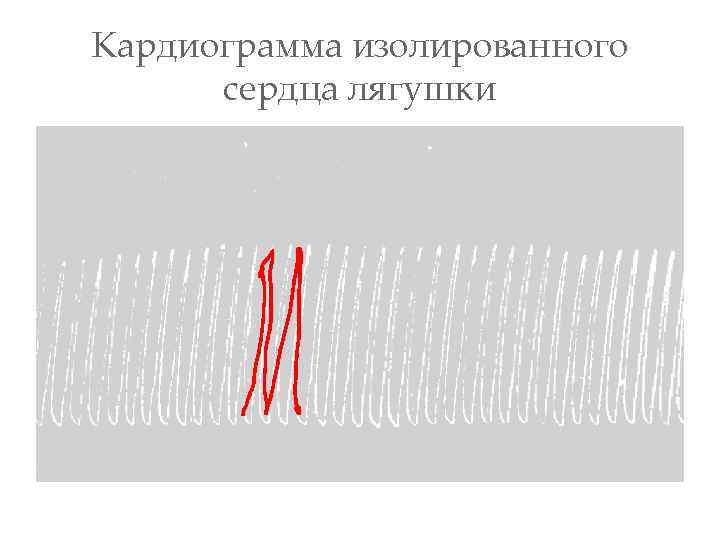

Кардиограмма изолированного сердца лягушки

Кардиограмма изолированного сердца лягушки